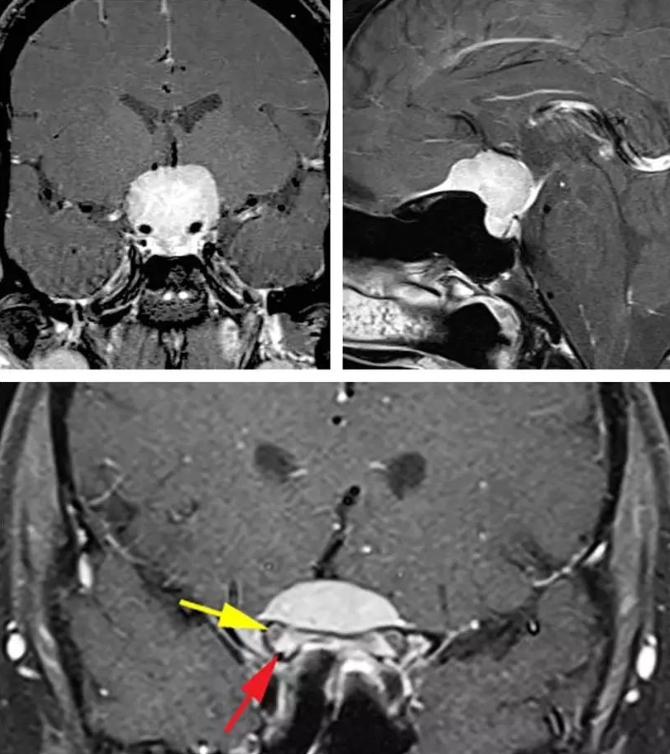

圖:典型的鞍結(jié)節(jié)腦膜瘤體積大并且擠壓、包繞血管。腫瘤的影像學(xué)表現(xiàn)也具有特征性:鞍內(nèi)不擴(kuò)大(左上圖)和額底可見腦膜尾征(右下圖)。下圖提示病變已經(jīng)累及雙側(cè)視神經(jīng)管,而且以右側(cè)為甚。紅色箭頭指的是視管內(nèi)強(qiáng)化的腫瘤,黃色箭頭則是指被移位的視神經(jīng)。